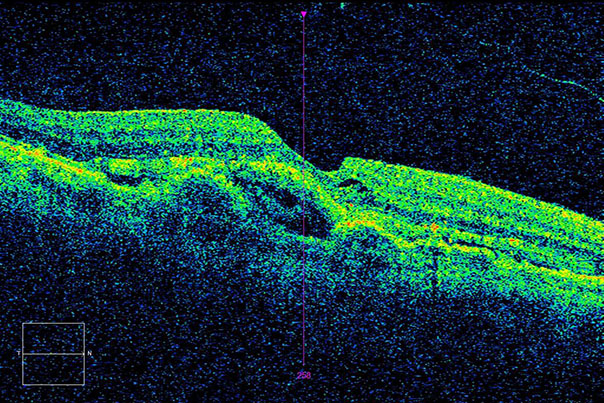

Влажная форма представлена в 15% всех выявленных случаев ВМД. Болезнь развивается быстро и часто приводит к значительной потере зрения. При влажной форме ВМД начинается процесс роста новых кровеносных сосудов (неоваскуляризация). Стенка таких сосудов пропускает жидкость и клетки крови, которые накапливаются в пространстве под сетчаткой. В результате гибнут клетки пигментного эпителия, возникают нарушения центрального зрения.

Именно оптическая когерентная томография позволяет получать наиболее качественные изображения сетчатки глаза, распознавая мельчайшие и самые ранние изменения, сопровождающие макулярную дегенерацию.

Оптическая когерентная томография (ОКТ) сканирует отдельные слои сетчатки, что позволяет выявить изменения внутри ткани и определить форму дистрофии.

Если при обычном офтальмоскопическом исследовании обнаруживается несоответствие остроты зрения и картины глазного дна, ОКТ позволит определить окончательный диагноз. Также данное исследование незаменимо для контроля эффективности проводимого лечения.